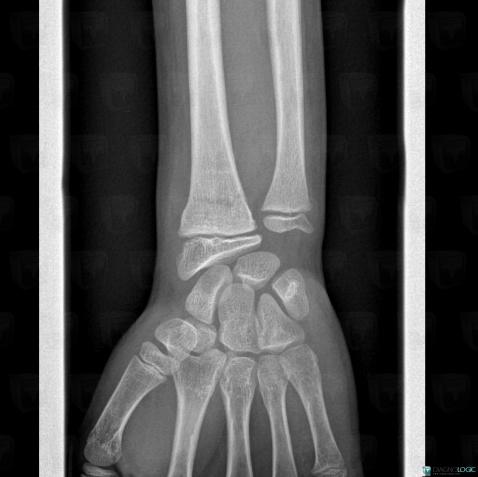

Posttraumatic, Radius - Distal part, X rays

Here is the specific information in the key image above:

- Diagnosis Posttraumatic, Location(s) Radius - Distal part, with gamuts sclerotic lines in metaphysis